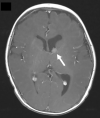

The Society for Cardiovascular Magnetic Resonance (SCMR) is an international society focused on the research, education, and clinical application of cardiovascular magnetic resonance (CMR). Case of the week is a case series hosted on the SCMR website ( https://www.scmr.org ) that demonstrates the utility and importance of CMR in the clinical diagnosis and management of cardiovascular disease. Each case consists of the clinical presentation and a discussion of the condition and the role of CMR in diagnosis and guiding clinical management. The cases are all instructive and helpful in the approach to patient management. We present a digital archive of the 2020 Case of the Week series of 11 cases as a means of further enhancing the education of those interested in CMR and as a means of more readily identifying these cases using a PubMed or similar search engine.